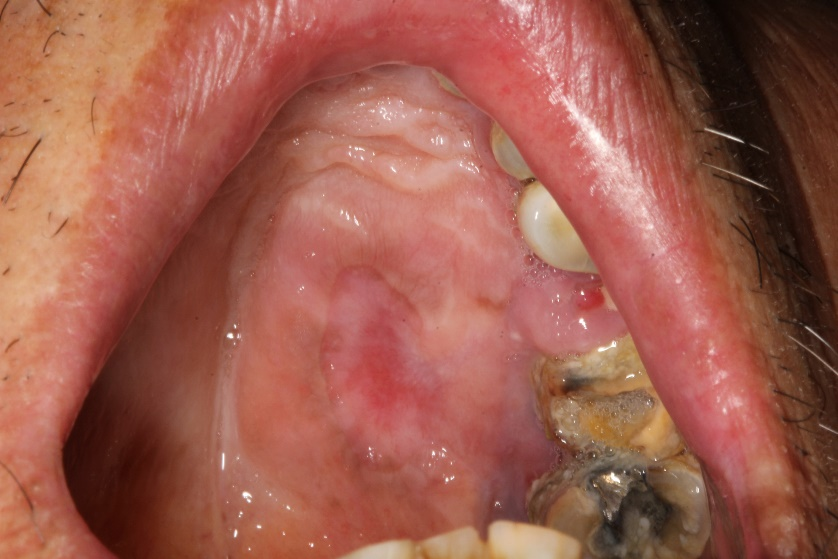

【求助】口腔黏膜病变 [病例帖]

图片尺寸2560x1920

患者男65岁,近来一周口腔粘膜不适,有糖尿病病史,空腹血糖在8.

图片尺寸3872x2592